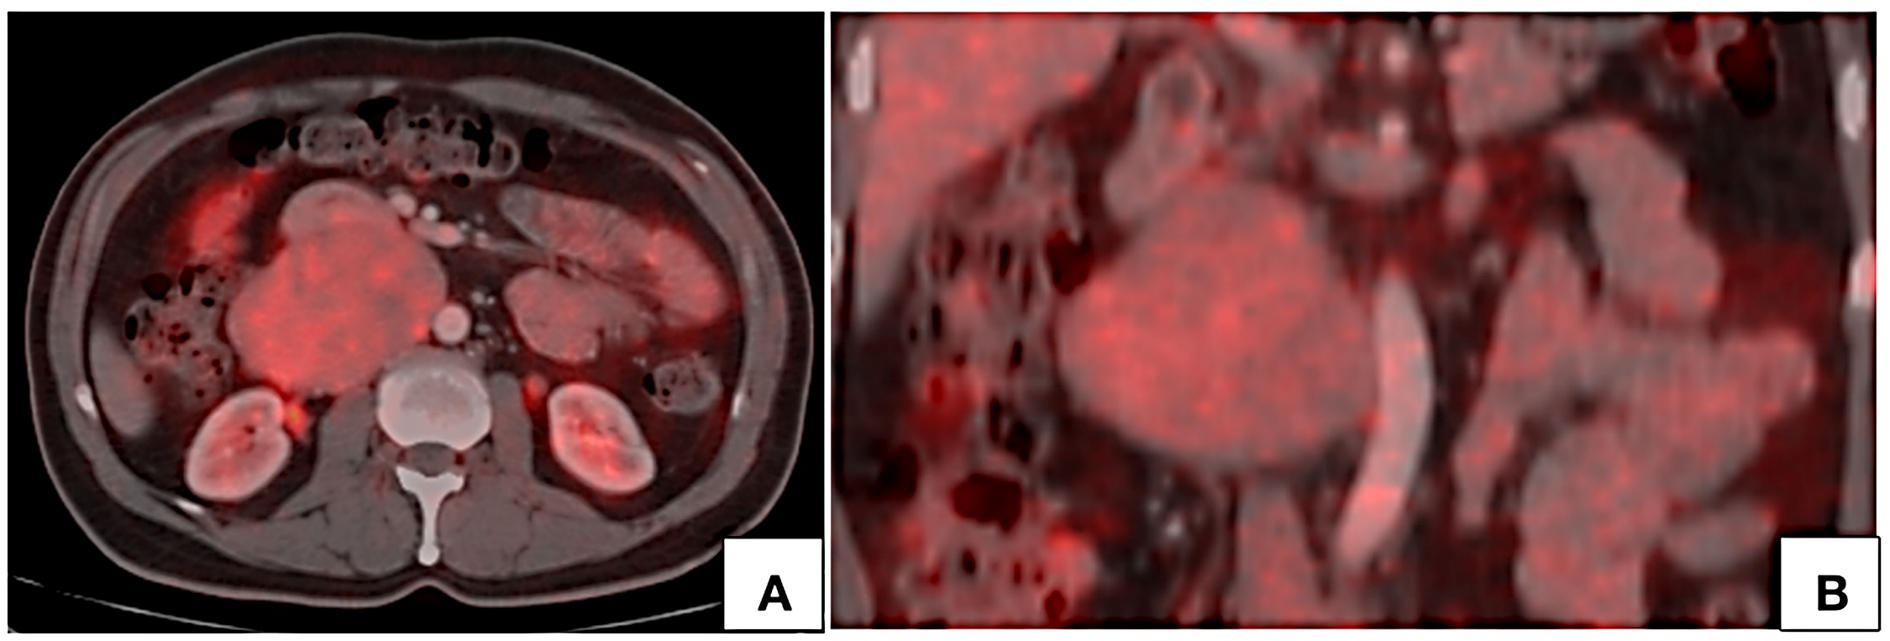

lumen at the site of maximum contact. However, proximal and distal segments of the inferior vena cava showed normal contrast opacification. Medially, the lesion was in relation to the abdominal aorta. Second and third part of duodenum and head of pancreas were displaced anterosuperiorly. Magnetic resonance imaging (MRI) showed a homogeneously enhancing circumscribed lesion in the retroperitoneum on right side of midline appearing isointense on T1W, hyperintense on T2W showing restricted diffusion. Few cystic areas were seen within the lesion. On prone imaging, the lumen of inferior vena cava was still imperceptible at the site of maximum contact. No obvious intraluminal extension was seen. Whole body positron emission tomography CT revealed mild FDG uptake with a maximum standard uptake value (SUVmax) of 4.1. No distant metastases were found.

On Positron emission tomography (PET), these tumors show mild to intense uptake of fluorodeoxyglucose (FDG) [21, 28, 29]. Singh N et al [28] presented a case of intraluminal LMS showing intense FDG uptake with SUVmax value of 18. In the above presented case, the lesion showed mild FDG uptake with an SUVmax value of 4. PET CT has an indispensable role in the evaluation of intraluminal tumors in differentiating tumor thrombus from bland nontumor thrombus since these tumors present with venous thrombosis. Another significant role of PET CT lies in assessment of spread. These tumors can be locally aggressive but distant metastases are uncommon. However, lung is the most common site of metastasis [2, 11, 14]. Metastasis to the liver and kidney have also been reported [11, 21].